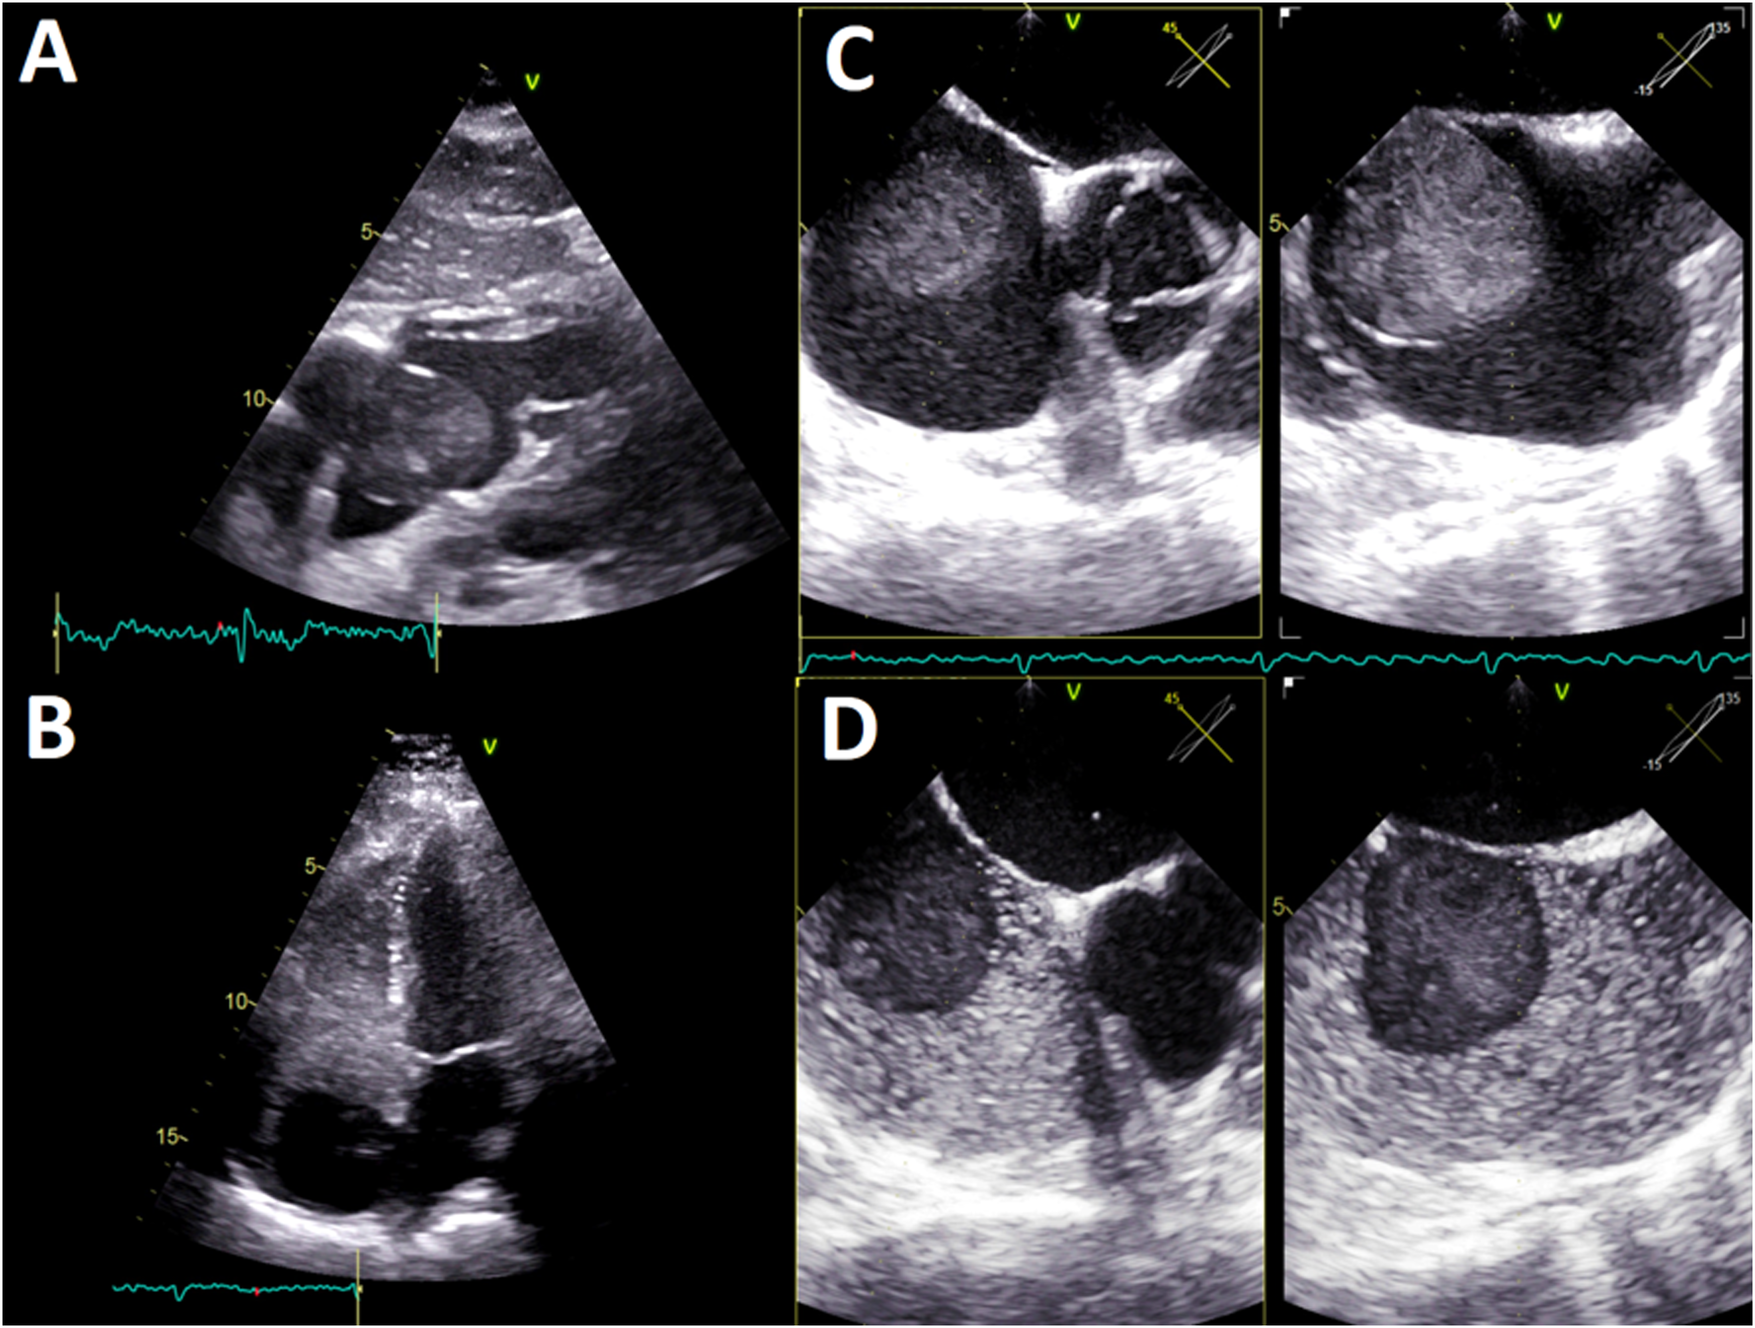

A cardiologic study plan was initiated with transthoracic echocardiography (TTE), which confirmed the presence of an anechogenic ovoid mass in the right atrium measuring 40 mm × 40 mm2, implanted in the interatrial septum without affecting the tricuspid valve (Figure 1A; Supplementary Video S1). In the study with agitated saline solution, echogenicity of the blood-like mass was evident (Figures 1B,D, Supplementary Video S2). No additional relevant findings were found.

Figure 1

(A) TTE, four-chamber subcostal view. Ovoid mass in the right atrium, with echogenicity almost blood-like and calcification areas. (B) TTE, four-chamber apical view. The agitated saline test shows an anechogenic, 40 × 40 mm2, mass in the right atrium implanted in the interatrial septum. No tricuspid valve compromise was observed. (C) TEE, multiplanar image of the interatrial septum (45°; 135°). A homogeneous pedunculated mass with a thin covering was implanted in the middle-low interatrial septum with pendulum movement. (D) TEE, multiplanar image of the interatrial septum (45°; 135°). The agitated saline test depicts anechogenicity of the hematic mass. TTE, transthoracic echocardiography; TEE, transesophageal echocardiography.

The TEE showed a homogeneous mass covered by a thin layer, implanted in the mid-low septum, and exhibited pendulum movement (Figure 1C, Supplementary Video S3). Furthermore, the previous dimensions were confirmed and no signs suggestive of vascularization were found. Given these findings, the diagnosis work-up was complemented with an ECG-gated CTA, displaying an ovoid, mobile mass of 35 mm in diameter with homogeneous content and calcified areas with a 12-mm pedicle adhered to the lower atrial septum near the coronary sinus ostium (Figure 2).

Within cardiac imaging studies, echocardiography is essential for the initial examination of intracardiac masses (1–3, 35, 36). It provides morphological information, data on the anatomical relationship, and determines the hemodynamic impact of the HEC. The cysts have particular ultrasound characteristics such as a thin reflective layer and an echolucent content, which could go unnoticed by novice explorers (9, 11). A meticulous analysis of our patient images confirmed these findings. The agitated saline solution study was useful because it highlighted the magnitude and dynamics of the mass, in addition to ruling out interatrial shunts. TEE describes with high precision anatomical aspects of atrial masses and defines carefully the components of a cyst, including the absence of vascularization, as seen in the images of this case (8, 9).